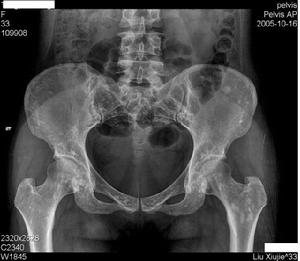

脆弱性骨硬化女,12岁。因跛行4月余就诊我院。体检:发育正常,体态均称,智力正常,轻度跛行。脊柱无明显侧弯及后突畸形,双坐骨神经行走区无压痛,双下肢直腿抬高试验(-),双髋部无肿胀,骨盆向左倾斜,双髋关节活动正常,双下肢等长。X线片示:脊柱腰段骨质未见明显异常,双侧髂骨、骶骨、股骨上段可见广泛分布卵圆形高密度钙化影,以双髋部明显,大小基本一致。CT扫描提示:双侧髂骨、耻骨、坐骨、股骨上段、骶骨可见广泛分布点状小结节状高密度钙化,骨小梁结构较紊乱。诊断:骨斑点症。因左股骨粗隆下骨钙化点较多,结构紊乱,行局部病变组织活检术。术中见皮下脂肪组织,髂胫束增生、硬化,骨膜与股骨骨质粘连,骨膜硬化,剥开骨膜见骨面粗糙,凹凸不平,突出骨质明显硬化,显露骨质未见明显破坏灶。病理活检提示皮下组织内见灶性黏液变性,骨膜纤维性增厚伴软骨化生,髂胫束内侧纤维软骨组织,未见致密影。 医学百科网 | YxBaike.Com

病史追查:检查患者父母及爷爷奶奶。X线透视下见双上肢、双肩、脊柱、双下肢骨质无明显异常。患者父亲及奶奶骨盆X线检查可见骶骨、髂骨、股骨上段多发性分布不均,大小不等,密度增高的圆形斑点状致密影,边缘清晰,大小约0.3cm2,与患者相似。[1] 医学百科网 | YxBaike.Com